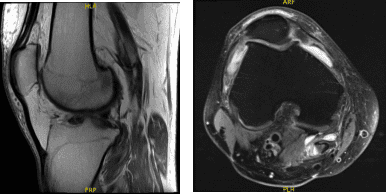

Un paciente de 57 años estaba en nuestra consulta con quejas relacionadas con dolor en la rodilla derecha. Probó fisioterapia y también medicamentos antiinflamatorios, que no le ayudaron. Le hicieron una resonancia magnética, que mostró un desgarro complejo del menisco mediano.

Resonancia magnética de rodilla derecha sin contraste